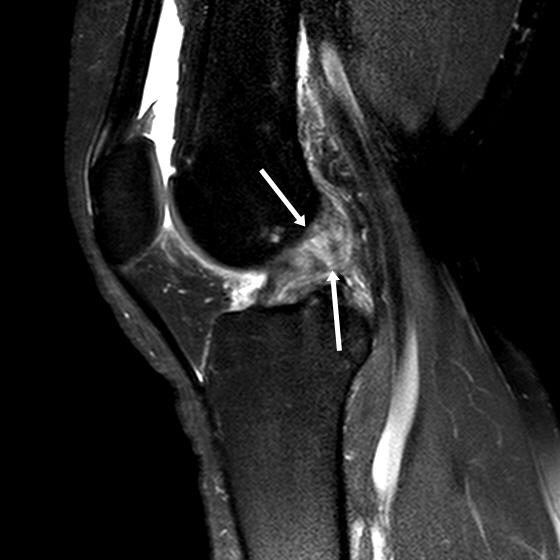

십자인대 파열은 X-ray검사에서 잘 나타나지 않으며, 관절내시경이나 MRI를 통해서만 확인이 가능하다. 운동을 하다가 통증과 함께 무릎에 이상이 느껴질 경우 반드시 전문의를 찾아서 정밀검사를 통해 확인하는 것이 좋다. 또한 통증 조절을 위한 적절한 약물치료와 물리치료가 도움이 되고 보조기가 적용될 수 있다.